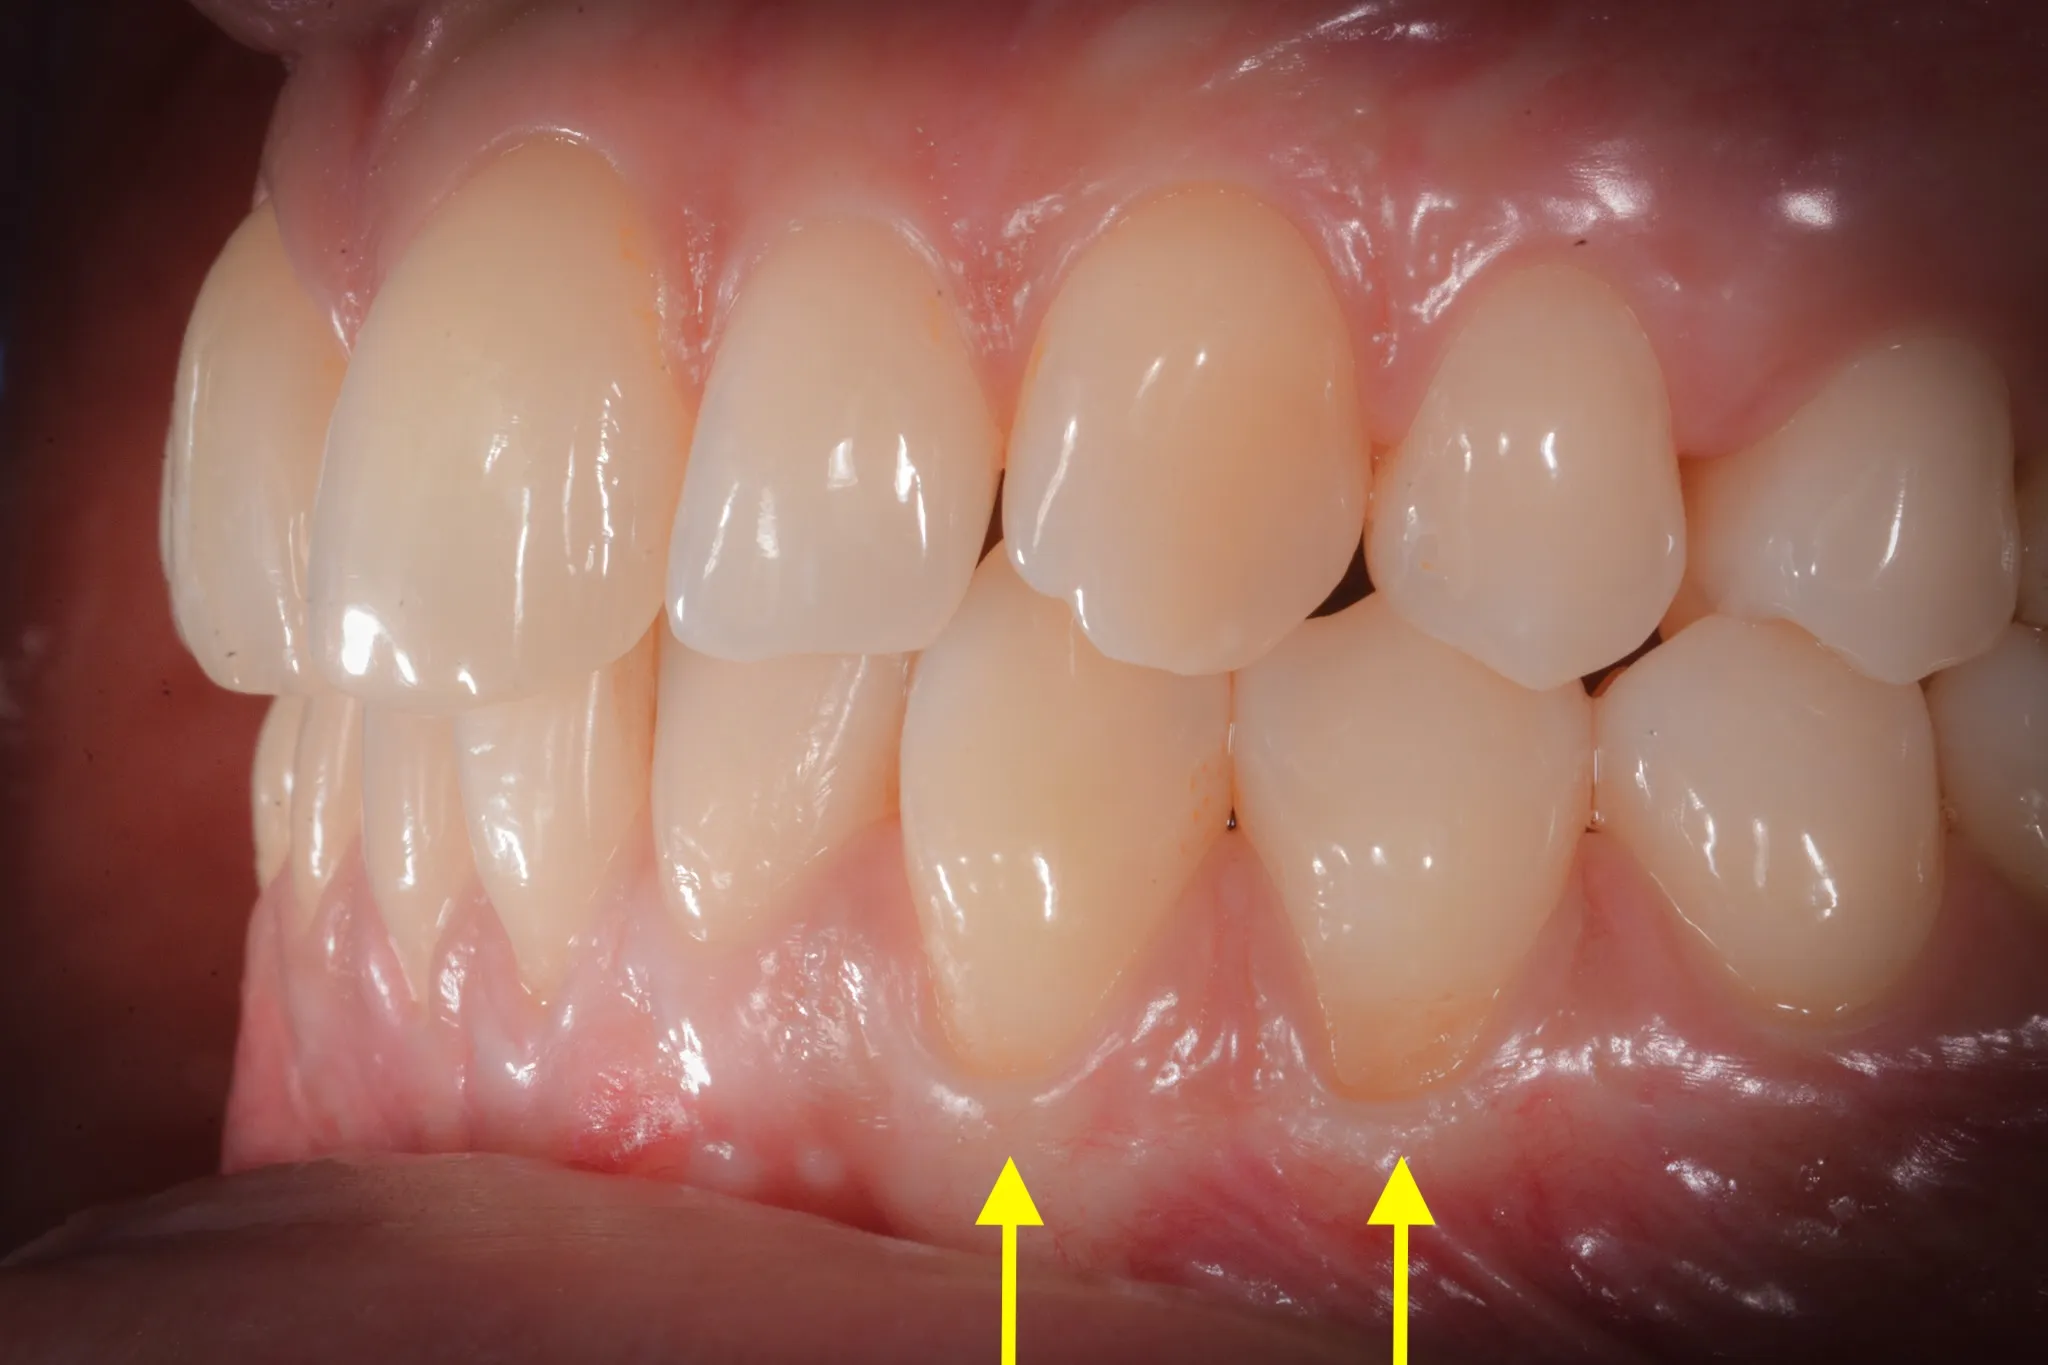

Il tessuto gengivale vero è un tessuto connettivo rivestito da epitelio cheratinizzato (in sostanza, un tessuto più spesso e resistente adeso all’osso sottostante). Quando si ritira, espone la radice del dente — una superficie che non è progettata per stare a contatto con l’ambiente orale. La radice è più porosa dello smalto, più vulnerabile alla carie, più sensibile agli stimoli termici.

Inoltre, a volte la gengiva si assottiglia per vari motivi lasciando spazio da un tessuto più delicato (mucosa orale) che è identico a quello che riveste le guancie e l’interno delle labbra.

Biotipo sottile. Alcune persone hanno gengive sottili per costituzione — una banda stretta di cheratinizzata, un periostio esile, una corticale ossea vestibolare ridotta a un velo. In questi pazienti, anche stimoli minimi possono innescare la recessione.

L’altro criterio molto importante è l’ampiezza del tessuto gengivale. Sotto i due millimetri, è consigliabile intervenire.